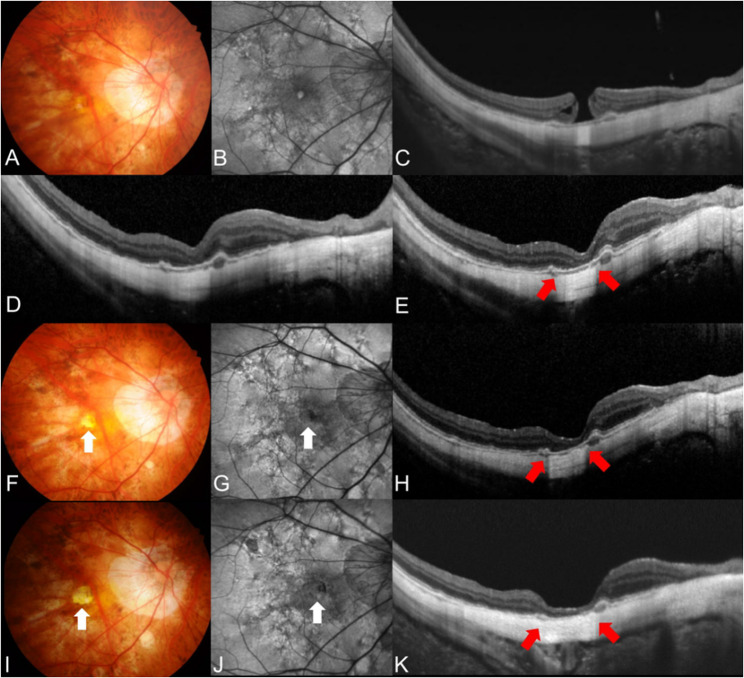

背景:探讨无视网膜裂的高度近视全层黄斑裂孔(FTMH)的临床特点和远期手术效果。方法:回顾性评价高度近视患者行玻璃体切除术联合内限制膜剥离和气体填塞治疗无视网膜裂的FTMH的手术效果。术后检查分别在术后1、3、6和12个月进行,进一步的随访间隔根据医生的判断进行调整。评估与视力和解剖成功相关的临床特征,定义为孔闭合而不发生中央凹萎缩。结果:纳入33只眼(30例),平均随访61.1±48.8个月。31只(93.9%)眼实现了黄斑孔闭合,其中16只(51.6%)眼在随访中出现中央凹萎缩。在整个随访期间,解剖成功眼的视力预后明显优于未解剖成功眼(P≤0.031),术后6个月、12个月和最后一次随访时的视力较基线有显著改善(P = 0.002, P)。结论:高度近视合并视网膜裂的FTMH患者玻璃体切除术后的闭孔率较高。然而,术后中央凹萎缩的发展阻碍了视力的改善。后葡萄肿,最小孔直径较大,轴向长度较长预示预后不良。

Results: Thirty-three eyes (30 patients) were included, and the mean follow-up period was 61.1 ± 48.8 months. Macular hole closure was achieved in 31 (93.9%) eyes, of which 16 (51.6%) developed foveal atrophy during follow-up. Eyes with anatomical success exhibited a significant better visual prognosis than those without during whole follow-up period (P ≤ 0.031), showing a significant postoperative visual improvement from baseline at 6 months, 12 months and final visit (P = 0.002, P < 0.001 and P = 0.013, respectively). Greater minimal macular hole diameter (P = 0.002) and the presence of posterior staphyloma (P = 0.040) were significantly related to anatomical failure, whereas longer axial length was significantly related to poorer final best-corrected visual acuity (P < 0.001).

Conclusions: Hole closure rate after vitrectomy in highly myopic patients with FTMH without retinoschisis was high. However, the postoperative development of foveal atrophy hindered vision improvement. Posterior staphyloma, greater minimal hole diameter, and longer axial length were predictive of poor prognosis.